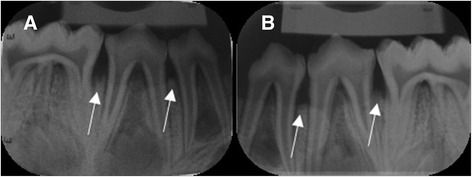

CBCT images were saved in DICOM standard format (version 3.0) and were imported to an open-source DICOM viewer (OsiriX 5.6, Pixmeo, Geneva, Switzerland), installed in an independent workstation (MacOS X v.10.6.8, Apple Inc., Cupertino, CA, United States). Analysis was performed independently and on separate occasions using an imaging post-processing protocol (OsiriX tool 3D-MPR, Pixmeo, Geneva, Switzerland). The images were analyzed simultaneously in axial, coronal, sagittal, parasagittal and circumferential views. Examiners were free to adjust brightness and contrast and to zoom in/out images, but not to apply filters. Figure 3a shows a sagittal section of control between PM2 and M1, 3B presents a two-hour lesion between PM2 and M1 and 3C shows a four-hour lesion between PM2 and M1. Figure 4a depicts a crater formed after 6-hour acid exposure between PM2 and M1 and 4B illustrates a vertical defect formed after 6 h of acid exposure between PM1 and PM2. Conventional intraoral radiographs were observed directly in a negatoscope inside a dark room. Examiners were free to use magnifying glasses. Figure 5a illustrates 6-hour lesion between M1 and PM2 and a control site between PM1 and PM2. Figure 5b shows four-hour lesion between PM1 and PM2 and two-hour lesion between PM2 and M1. There was no time limit for viewing radiographs or CBCT images.

Fig. 5.

Periapical radiographs. a. Six-hour lesion between first molar and second premolar. No lesion (control) between first and second premolar. b. Four-hour lesion between first and second premolar. Two-hour lesion between second premolar and first molar